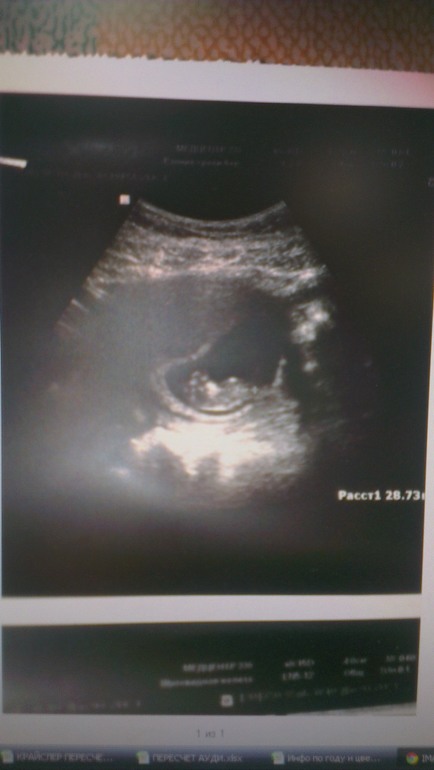

ФолликулометрияВчера просто скрючело попалам ,позавчера делала узи,врач ничего ужасного в общем не говорила.я не бегала,не прыгала ,все 10 недель было все прекрасно ,даже намека не было на тонусы.А вчера даже простите пописать не могла .Я прекрасно понимаю ,что с такими вопросами к врачу .Так что очень прошу без лекций и так фигово ,выкидыш в том году уже был.Пожалуйста если кто то понимает ,что то напишите.

Форма матки и затемнение вокруг действительно указывают на тонус, но слава Богу тонус по другой стенке от малыша. Но снять его все равно надо.